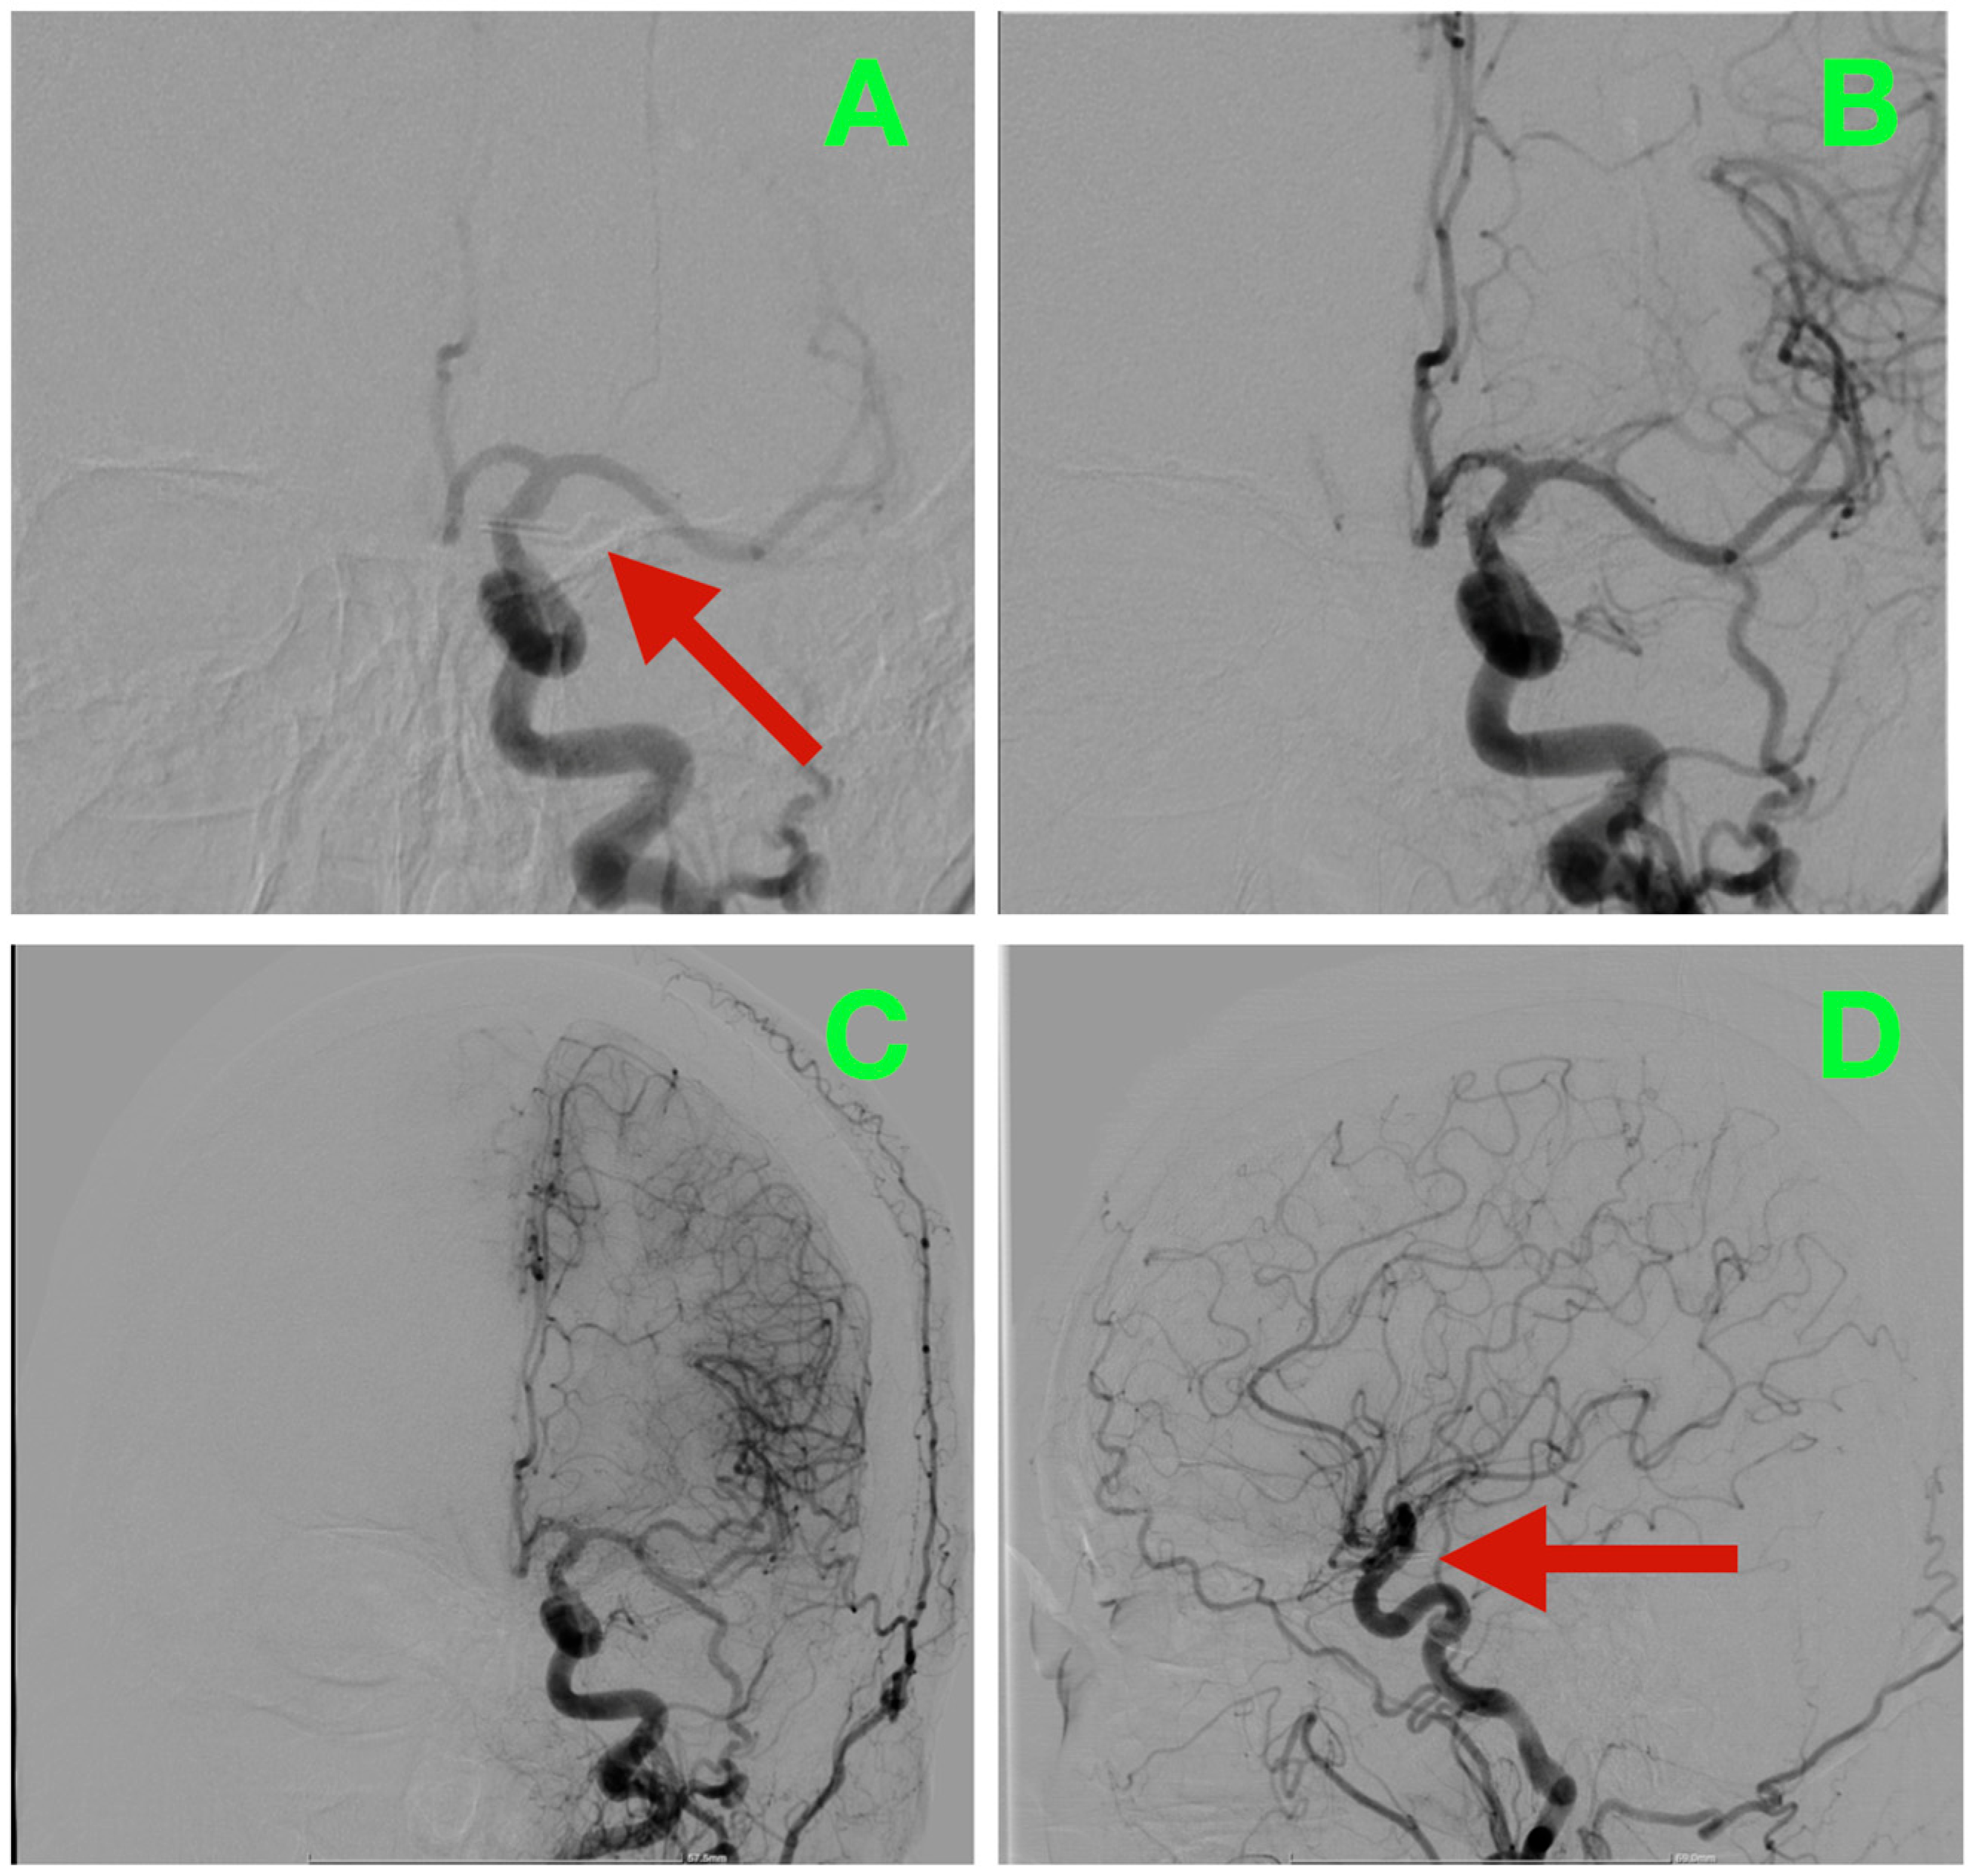

Catheter digital subtraction angiography (DSA) in anteroposterior oblique and lateral views (Figure 1A,B), supplemented by 3D rotational angiography (Figure 2A–D), demonstrated a left ICA-PCoA junction aneurysm originating from the communicating (C7) ICA segment and extending posteriorly into the carotid–optic cistern. Three-dimensional quantitative measurements of the aneurysm size demonstrated a maximum sac height of 13.1 mm, maximum sac width of 10.0 mm and maximum neck diameter of 4.3 mm, producing an aspect ratio of 3.06 and dome-to-neck ratio of 2.34. The aneurysm had a bilobed morphology with a smaller posterior superior daughter sac located along the posteromedial neck quadrant precisely adjacent to the PCoA origin and its associated perforator field—where even minimal posterior clip torque would pose a threat to the thalamoperforators.

Figure 2.

Three-dimensional rotational angiography with volume rendering and surgical measurements. (A): Quantitative reconstruction showing height 13.1 mm, width 10.0 mm, neck 4.3 mm (aspect ratio ≈ 3.06; dome-to-neck ≈ 2.34). (B): Oblique “working” view highlighting the posteriorly oriented, bilobed sac and its relationship to the carotid–optic window; the dome nests beneath the optic apparatus, forecasting a narrow margin for superior blade trajectory. (C): True lateral working view delineating the PCoA take-off and the posteromedial perforator bed abutting the neck, the critical zone to be visualized during neck dissection and clip deployment. (D): AP volume render situating the aneurysm within the opto-carotid cistern, illustrating the clearance required for clip passage while maintaining PCoA and anterior choroidal patency and avoiding posterior wall torque toward the perforators.

Combining the geometric and spatial parameters of this aneurysm with the relationship of the optic and carotid arteries defined a posteriorly projecting aneurysm below the optic apparatus, making it suitable for a traditional pterional craniotomy with early cisternal decompression, 360-degree delineation of the neck and a clip line parallel to the take-off of the PCoA.